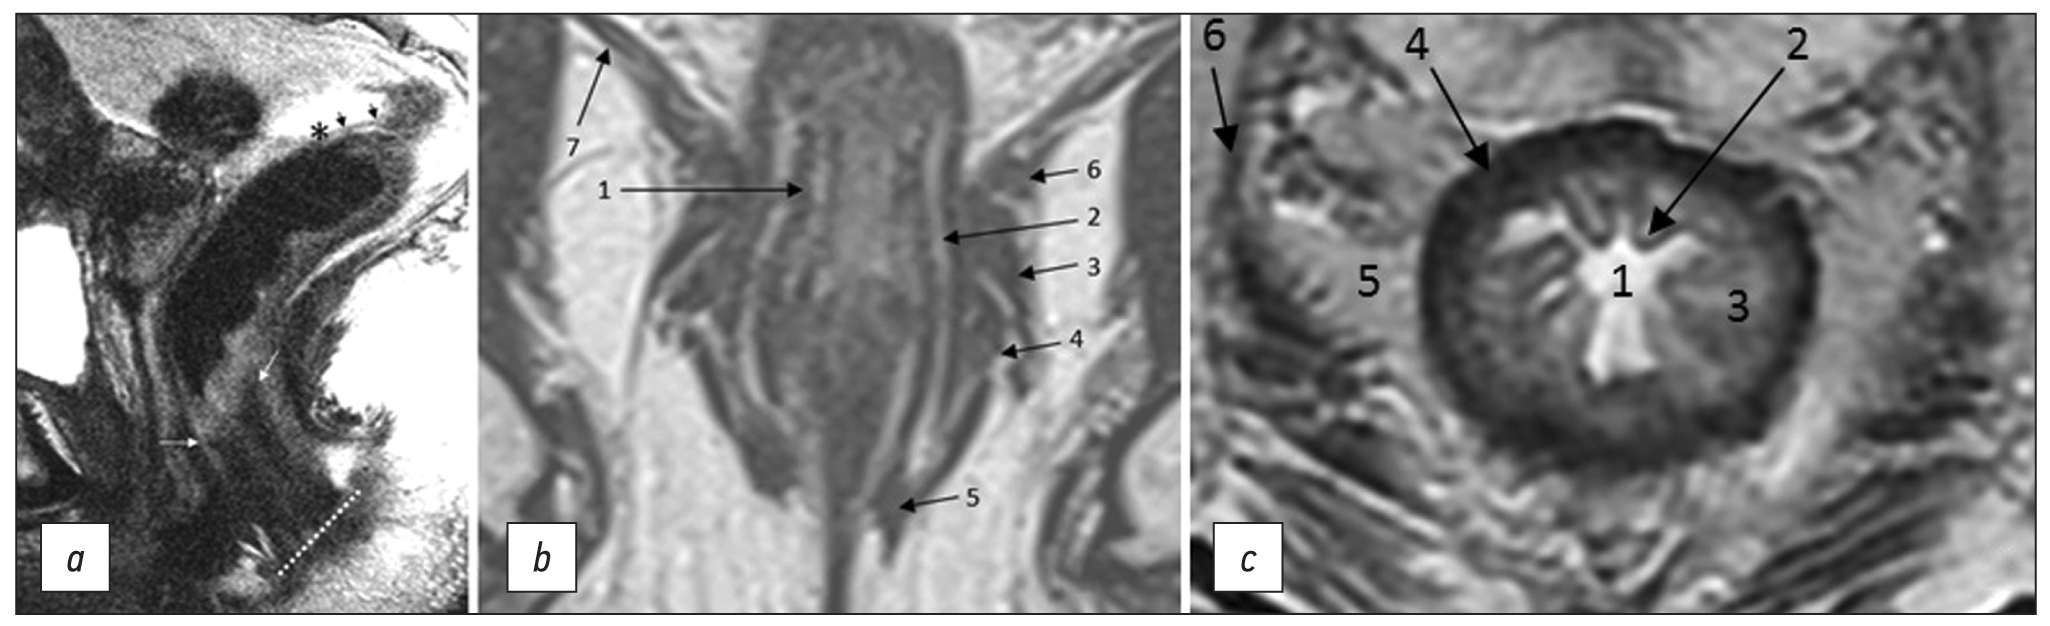

Conventional magnetic resonance imaging of peripheral nerves: MR-neurography

Abstract

Peripheral neuropathy is known to be one of the most common neurological disorders. Despite the great diagnostic value of electroneuromyography and ultrasound, addressing the diagnostics and differential diagnostics of peripheral nerve diseases of different origin could be challenging. In recent years, magnetic resonance tomography has been increasingly used for evaluating cases of suspected or established peripheral neuropathy with excellent results.

This manuscript mainly deals with the advantages and limitations of the aforementioned diagnostic instruments, technical considerations according to different anatomy of peripheral nerves, along with state-of-the-art technical decisions, frequently used magnetic resonance imaging sequences and their diagnostic value based on own observation, and recommendations for contrast enhancement use and different methods of fat suppression.

Currently, there is practically no standardized description of normal magnetic resonance imaging features of peripheral nerves, as well as their changes in different diseases. The evaluation of images is mainly based on the radiologist experience, which obviously decreases method’s diagnostic value. Studies of large numbers involving healthy volunteers and patients with peripheral neuropathies of different origin are required to address this issue.

356-368